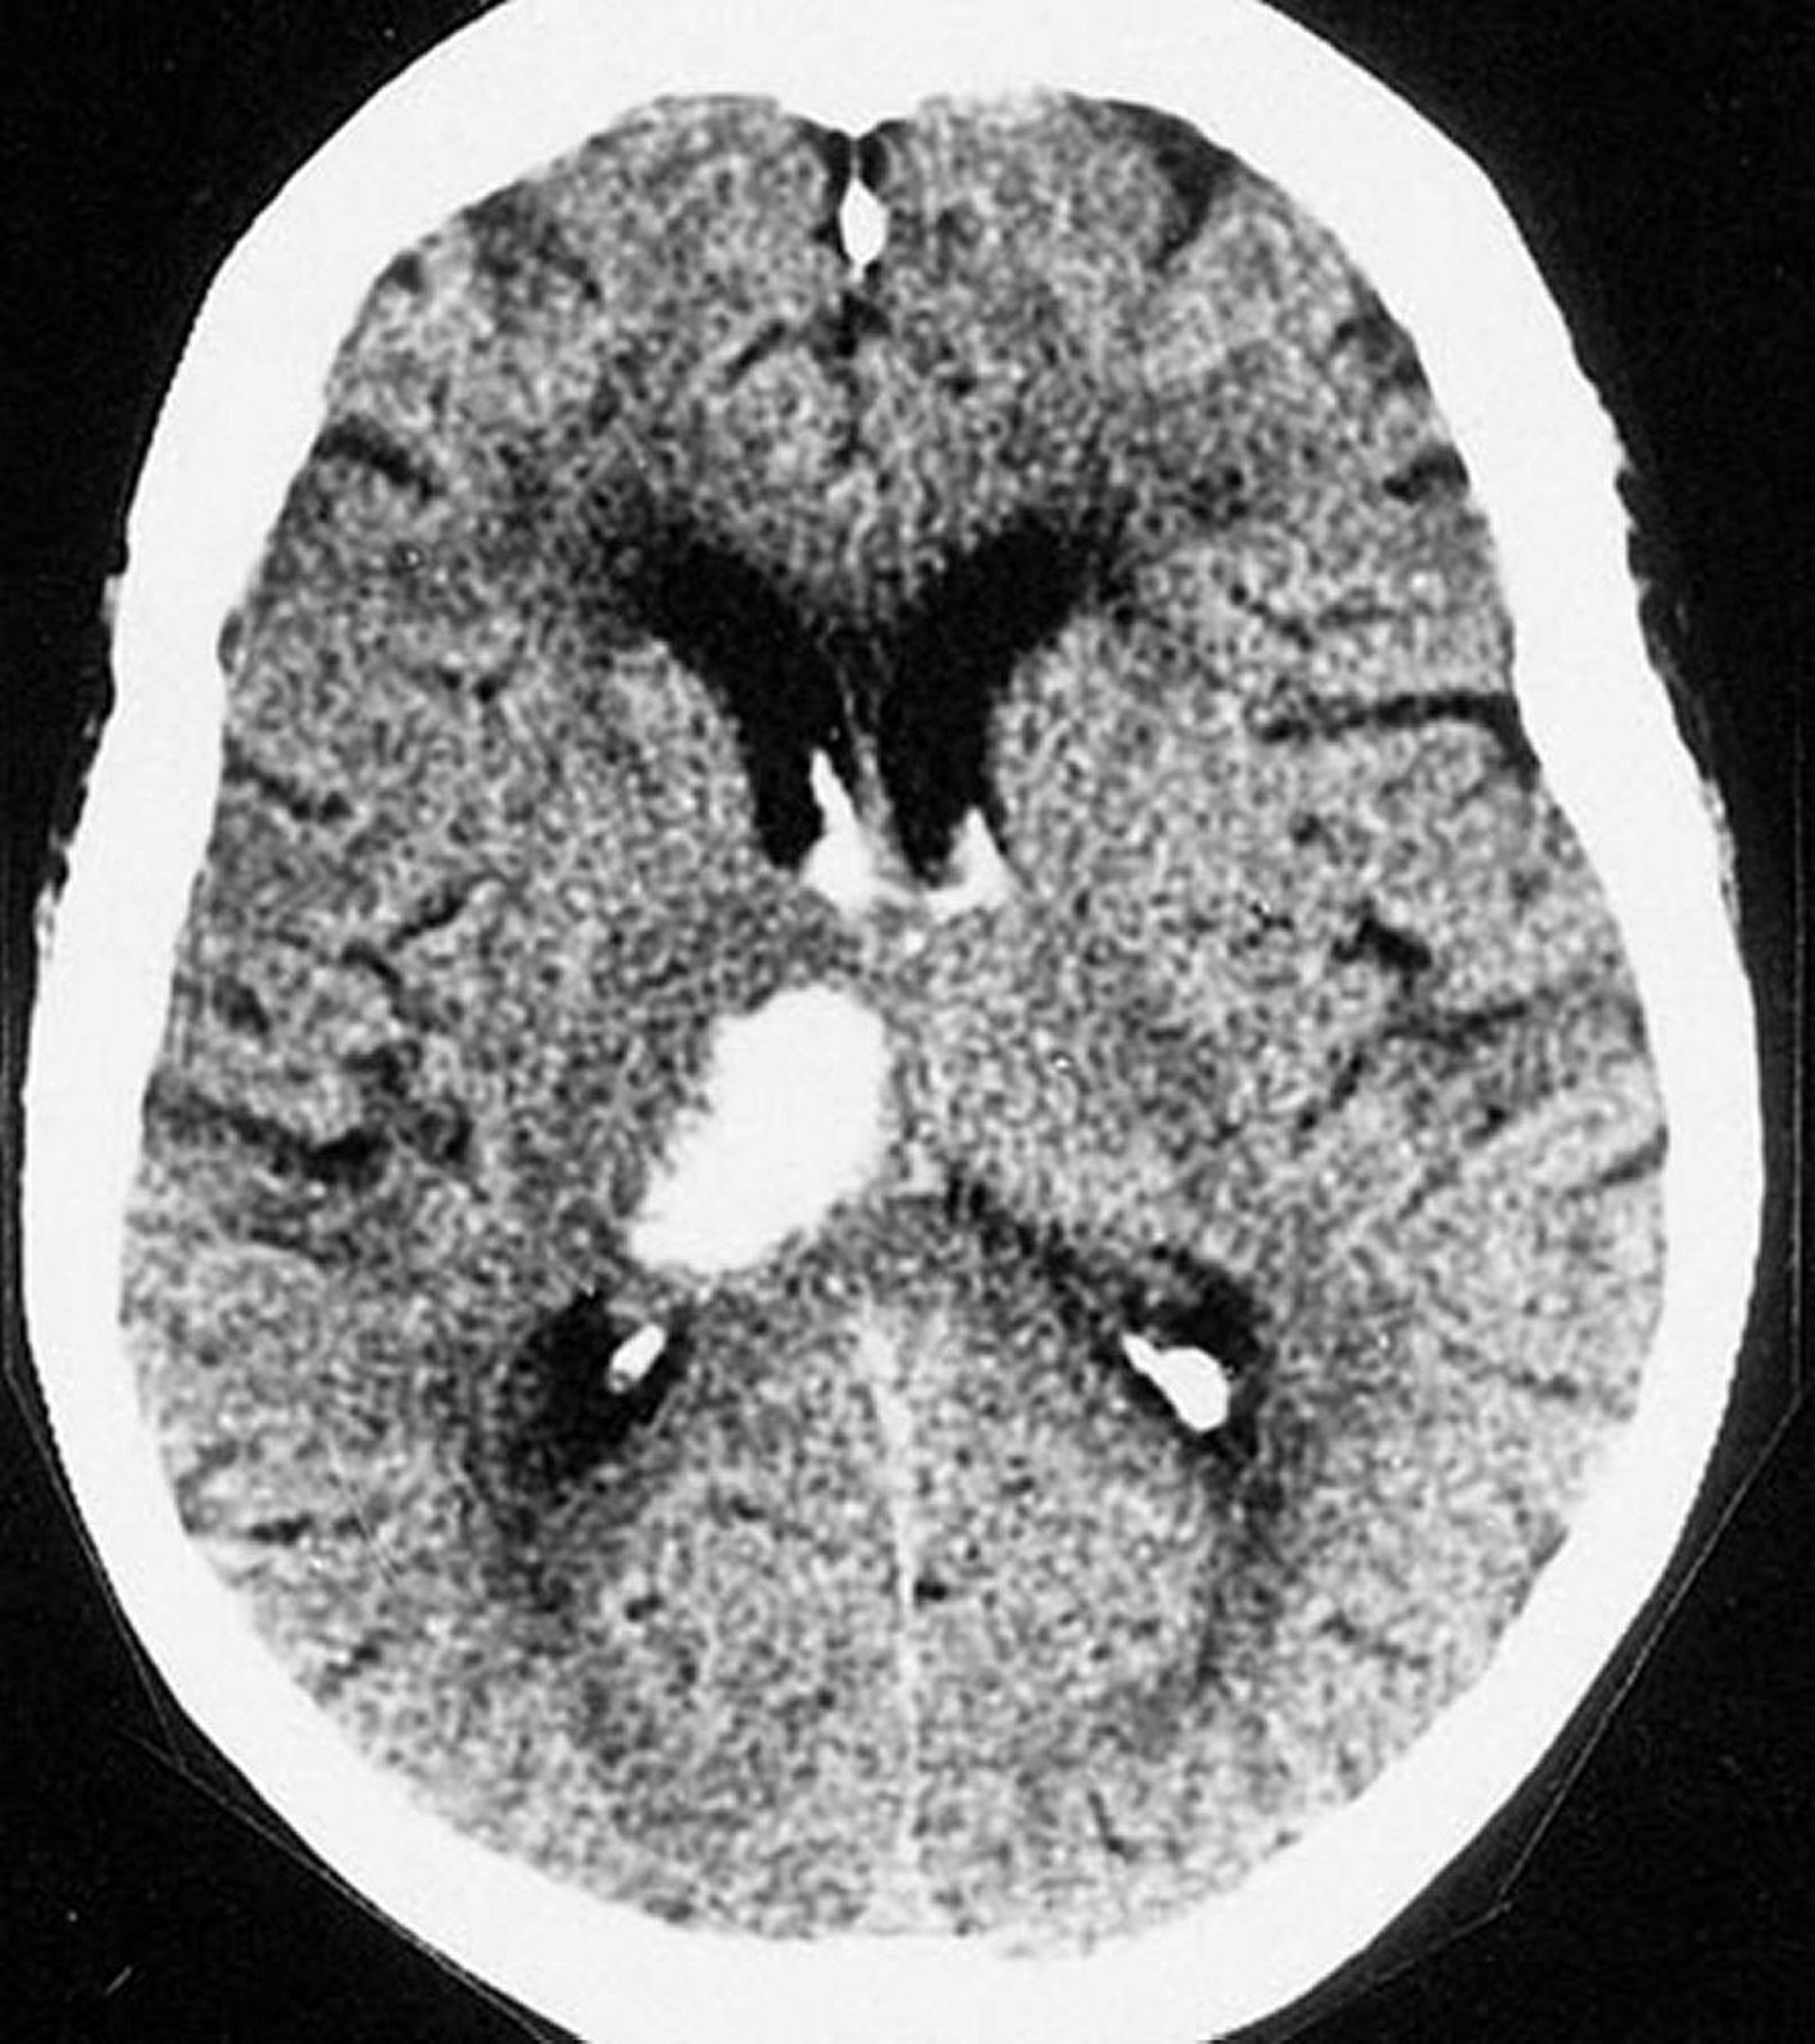

Die erhöhte Dichte im linken Gehirn auf diesem nicht kontrastverstärkten CT ist konsistent mit einer intrazerebralen Blutung.

© 2017 Elliot K. Fishman, MD.

Diese CT-Aufnahme zeigt eine Blutung im Thalamus. Intrazerebrale Blutungen treten am häufigsten im Thalamus und in den Basalganglien auf.

By permission of the publisher. From Furie K, et al. In Atlas of Clinical Neurology. Edited by RN Rosenberg. Philadelphia, Current Medicine, 2002.